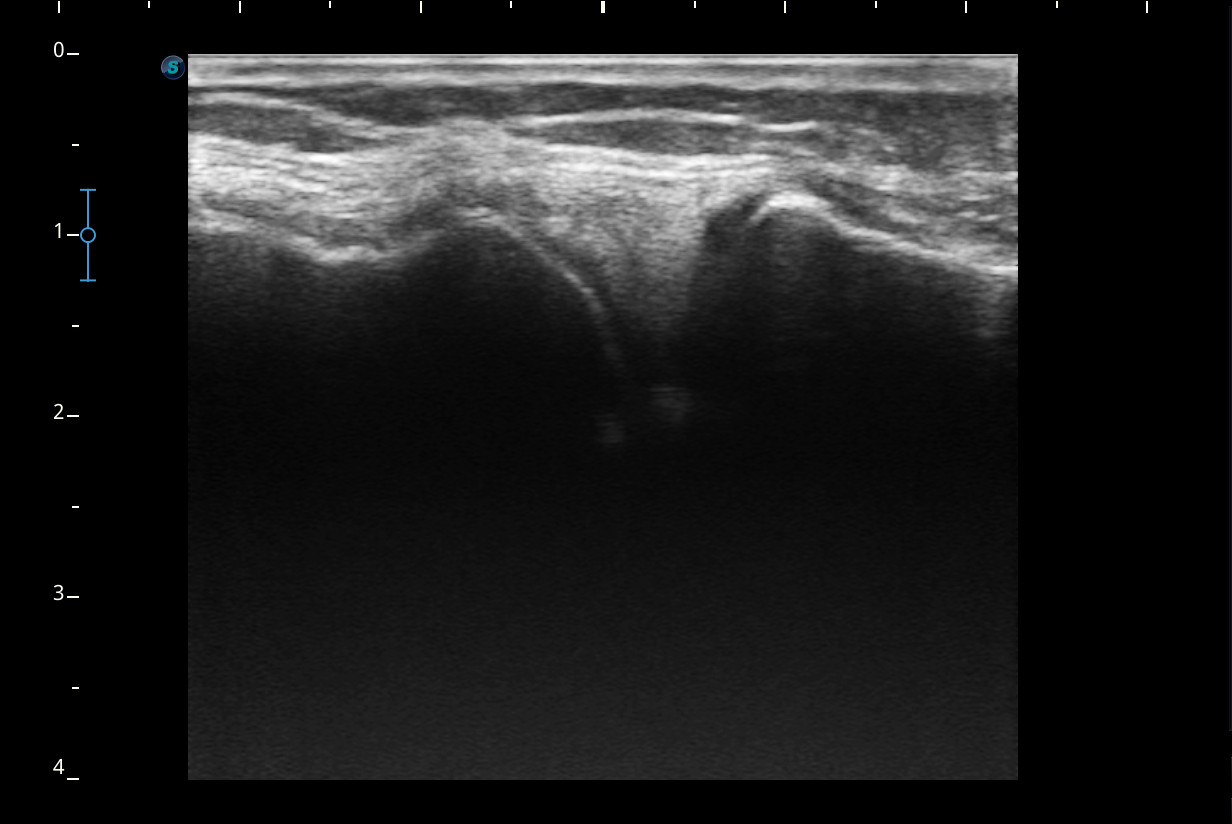

Rodilla sin derrame articular. No se aprecian lesiones en Ligamentos colaterales. Ligamento rotuliano sin hallazgos valorables. Rotura menisco interno y dudosa fisura menisco externo. Tendones rotuliano y cuadricipital normales.

Resonancia magnética confirma rotura cuerno posterior menisco interno.

Rotura cuerno posterior menisco interno.